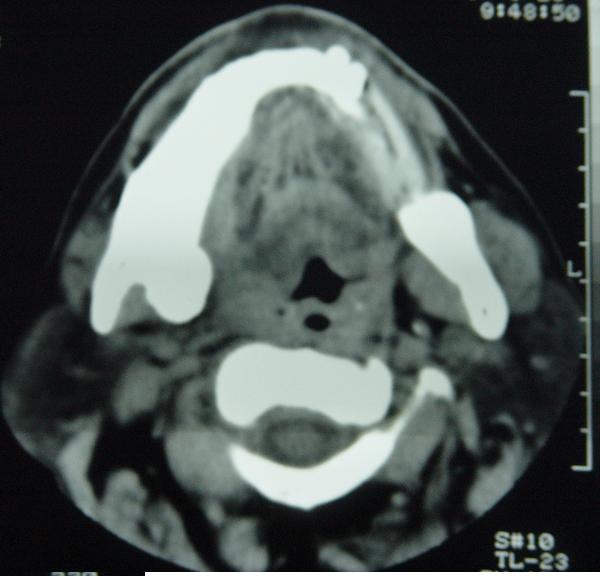

标题: CT12465:下颌骨肿瘤,请会诊 [打印本页]

标题: CT12465:下颌骨肿瘤,请会诊

发现下颌骨肿瘤近30年.逐渐增大.

考虑右侧下颌骨水平部及升部骨纤维异常增殖症可能性大。

考虑右侧下颌骨骨化性纤维瘤。